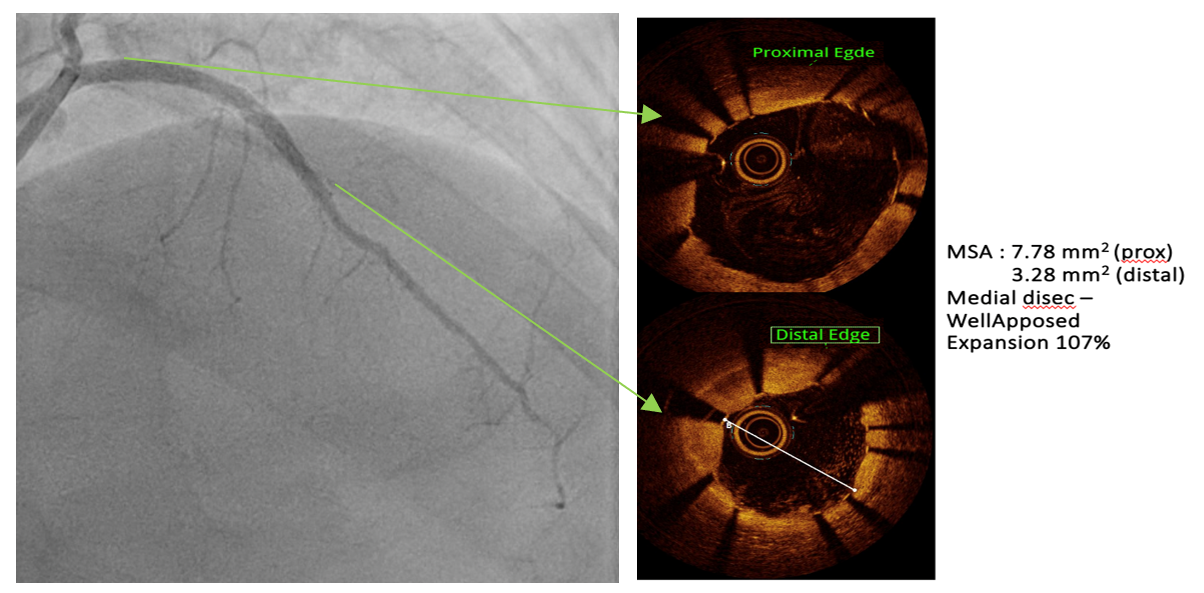

PCIof the LAD was performed via femoral access using a BL 3.5/7F guiding catheter.A Runthrough Hypercoat wire was advanced distally without difficulty. The OCTcatheter failed to cross the lesion, and a 2.5 ¡¿ 15 mm scoring balloon couldnot pass the mid LAD. A microcatheter was inserted, and the wire was exchangedfor a Rotawire. Rotational atherectomy was performed using a 1.25 mm burr withshort, gentle pecking runs at 180,000 rpm, followed by upsizing to a 1.5 mmburr for three runs at 200,000 (2 times) and 160,000 rpm. The burr advancedsmoothly with improved tactile feedback, suggesting successful plaquemodification. The wire was exchanged back to a Runthrough, and OCT (DragonflyOPTIS) imaging showed an MLA of 1.43 mm©÷ at mid LAD with severe 360¡Æ calcification(0.9 mm thick, 41 mm long) and a napkin-ring pattern. A 2.5 ¡¿ 15 mm cuttingballoon was used with multiple 14–18 atm inflations, producing a visible¡°crack¡± in the calcified cap. Angiography and repeat OCT confirmed the calciumfracture. A 3.0 ¡¿ 46 mm DES was deployed from the ostial to distal LAD at 14atm and post-dilated with a 3.5 mm NC balloon proximally. Final angiographyshowed TIMI 3 flow. OCT demonstrated excellent stent expansion (MSA 7.78 mm©÷proximal, 3.28 mm©÷ distal) without dissection and with 107% stent expansion.